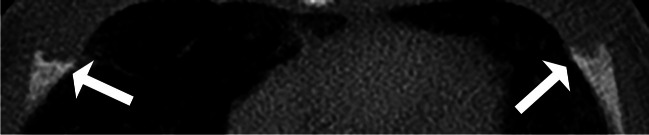

Materials and methods: A 15-year retrospective study was conducted on children under 2 years of age who underwent chest and abdominal computerized tomography (CT) scans for pneumonia, fever, congenital lung disease, pain, or appendicitis. Randomized selection included 120 chest and 120 abdominal CT scans. Demographic and clinical information was obtained from medical record reviews. Two pediatric radiologists independently reviewed the studies and indicated the presence and location of costochondral junction variation patterns (spurs), and fissure, horizontal lucency, corner, or bucket handle as identified on two consecutive slices on axial views. Disagreements were resolved by a third radiologist. We excluded patients with underlying medical conditions that could affect the skeleton and studies with motion artifacts. A t-test was used to evaluate the relationships between age, CT slice thickness, and the diagnosis of costochondral junction variations. Kappa statistics were used to evaluate agreement.

Results: A total of 123 children were excluded due to motion artifacts (n = 30), trauma (n = 31), being evaluated for child abuse (n = 3), slice thickness of 5 mm (n = 1), and underlying medical conditions (n = 58). The final group included 117 children (73 males and 44 females) with an average age of 1 year; 64 had chest and 53 abdominal CT scans. Agreement was fair (kappa = 0.29) at the patient level and poor at the rib level (kappa = 0-0.64). The final number of variations, after resolving disagreements with a third radiologist, was 46 of costochondral junction variations in 19 children (16.2%, 19/117); all were costochondral junction spurs at the levels of the second to eighth ribs. Costochondral junction variations were significantly more common in younger children (average 0.7 ± 0.6 years vs. 1.1 ± 0.6 years, P = 0.024) and when there was thinner CT slice thickness (average 1.6 ± 1.4 mm vs. 2.5 ± 1.5 mm, P = 0.041).

Conclusion: Costochondral junction variations were identified in 16.2% of children under 2 years of age, and some may mimic healing costochondral junction fractures. There was only fair agreement between radiologists.